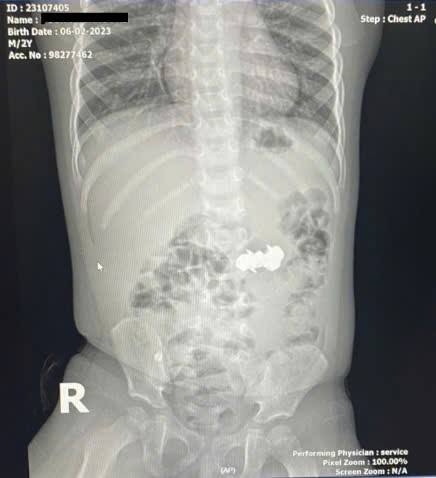

Baby DHP (2 years old, residing in Nghe An) was brought to the hospital by his family in a state of suspected ingestion of a foreign object while playing with a toy. Abdominal X-ray results showed four small, round, sharp-tipped metal objects in the abdomen, suspected to be magnetic nails. These magnets had stuck together in the digestive tract, creating a particularly serious risk.

Foreign object suspected to be magnetic nail.